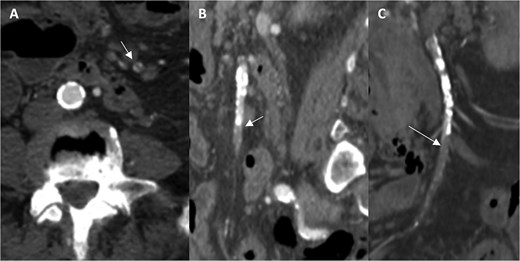

A 76-year-old female patient with a medical history of diabetes mellitus and cholecystectomy presented to the emergency department with a 7-month history of postprandial abdominal pain, food fear, and weight loss (25–30 kg). Over the past 3 days she referred symptom worsening to constant pain. On the physical examination, the abdomen was tender to palpation. Laboratory results revealed leukocytosis (13.700/μl), high C-reactive protein (23 mg/dl) and lactate 0.7 mmol/L. A previously performed computed tomography angiography (CTA) in context of a lithiasic cholecystitis revealed celiac trunk occlusion and pre-occlusive stenosis of the SMA ostium but the patient was not referred for a vascular surgery consultation. A CTA scan obtained in the emergency department revealed thrombotic occlusion of the SMA origin associated with distal embolization (Fig. 1A–C). In this context, the diagnosis of acute-on-chronic mesenteric ischemia was assumed, and the patient was proposed for urgent endovascular revascularization. A 7F (French) sheath was placed via percutaneous access in the left brachial artery, and SMA catheterization was performed using a triaxial system (sheath, MP catheter and Progreat® catheter). Diagnostic angiography confirmed the CT findings (Fig. 2A). Catheter-directed thrombolysis was first performed with a 5 ml bolus of alteplase, followed by percutaneous thrombectomy using the Penumbra® system (Fig. 2B), with retrieval of fresh thrombus (Fig. 3). Primary stenting of the SMA ostium was also performed using an Advanta® 6 × 39 mm stent with proximal flair, with an excellent imagological result (Fig. 4A and B). The postoperative course was uneventful, with significant improvement of symptoms and clinical status. A CTA prior to discharge revealed a patent stent with proper placement and no evidence of residual thrombus (Fig. 5A and B). The patient was discharged on the seventh postoperative day with apixaban 5 mg twice daily. Follow-up of the patient at 6 months revealed that the stent remained patent, with no reported abdominal complaints. The patient gained 15 kg at this point of follow-up.

Computed tomography angiography images demonstrating occlusion of the superior mesenteric artery in the axial (A), sagittal (B), and coronal planes (C; arrows indicating the thrombus).